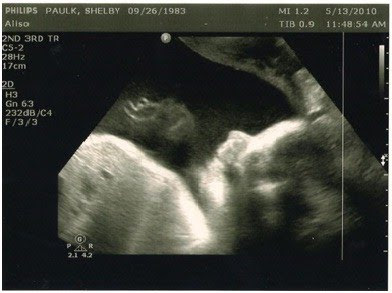

Baby’s heart rate was in the 140s and when she measured me I was measuring at 35 weeks–pretty big, especially considering 2 weeks ago I was measuring right on (then, at 29 week) so she sent me over for an ultrasound just to make sure the baby wasn’t too big and to make sure I didn’t have too much fluid. The ultrasound went very well and we even got to see her in 4D–baby definitely has Ty’s squinty eyes!! We had her look again, just in case, but this time are reassured 100% that our third little peanut is definitely a girl!

It’s hard to tell in this picture but she was smiling!! It was so cute…

Amazing how you can see her cute squishy nose and pretty lips! Hope you can take advantage of the chiropractor or massages soon – they should definitely help!